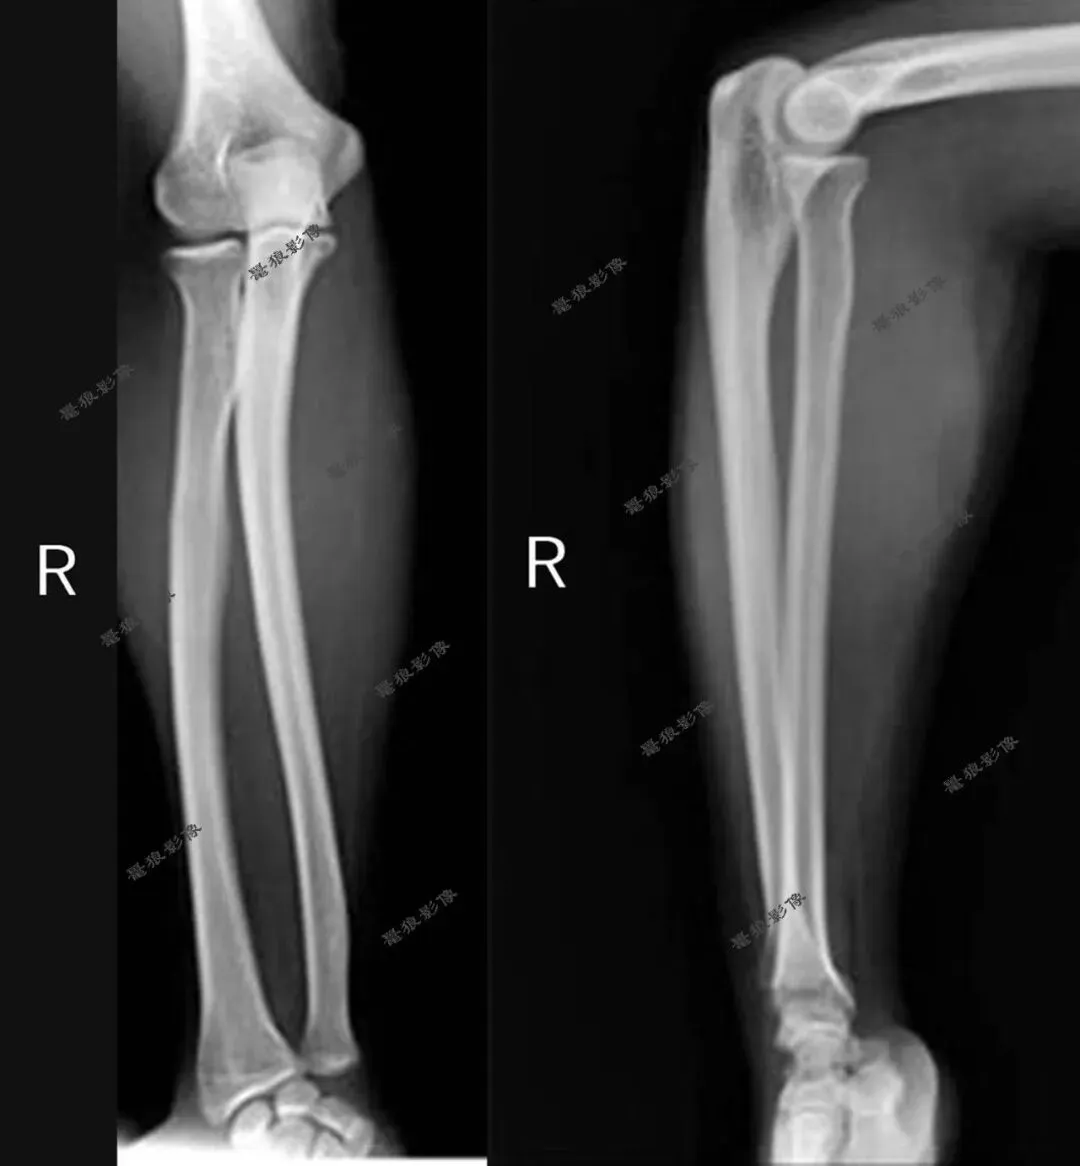

一、先来看几组图片

我们再看肘关节几组图片